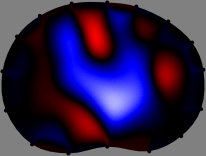

Refer to caption

Figure 2: Fidelity-embedded regularization method. (Left bottom) Correlations between four different column vectors (𝐒ksubscript𝐒𝑘{\bf S}_{k}) and all the remaining column vectors (𝐒subscript𝐒{\bf S}_{\ell}) are visualized. (Right bottom) Performances of the proposed fidelity-embedded regularization method for λ=𝜆\lambda=\infty are shown by numerical simulations.

To explain the FER method, we closely examine the correlations among column vectors of the sensitivity matrix 𝕊𝕊\mathbb{S}, described in Fig. 2. The correlation between 𝐒ksubscript𝐒𝑘{\bf S}_{k} and 𝐒subscript𝐒{\bf S}_{\ell} can be expressed as

for i=1,,16𝑖116i=1,\cdots,16[23]. This shows that the column vector 𝐒ksubscript𝐒𝑘{\bf S}_{k} is like an EEG (electroencephalography) data induced by dipole sources with directions uj,j=1,,16formulae-sequencesubscript𝑢𝑗𝑗116\nabla u_{j},j=1,\cdots,16 at locations ΔksubscriptΔ𝑘\Delta_{k}. Given that two dipole sources at distant locations produce mutually independent data, the correlation between 𝐒ksubscript𝐒𝑘\mathbf{S}_{k} and 𝐒subscript𝐒\mathbf{S}_{\ell} decreases with the distance between ΔksubscriptΔ𝑘\Delta_{k} and ΔsubscriptΔ\Delta_{\ell}. Fig. 2 shows a few images of the correlation 𝐒k,𝐒(|𝐒k||𝐒|)1subscript𝐒𝑘subscript𝐒superscriptsubscript𝐒𝑘subscript𝐒1\left\langle\mathbf{S}_{k},\mathbf{S}_{\ell}\right\rangle(|\mathbf{S}_{k}||\mathbf{S}_{\ell}|)^{-1} as a function of \ell for four different positions ΔksubscriptΔ𝑘\Delta_{k}. The correlation decreases rapidly as the distance increases. In the green regions where the correlation is almost zero, 𝐒subscript𝐒{\bf S}_{\ell} is nearly orthogonal to 𝐒ksubscript𝐒𝑘{\bf S}_{k}.